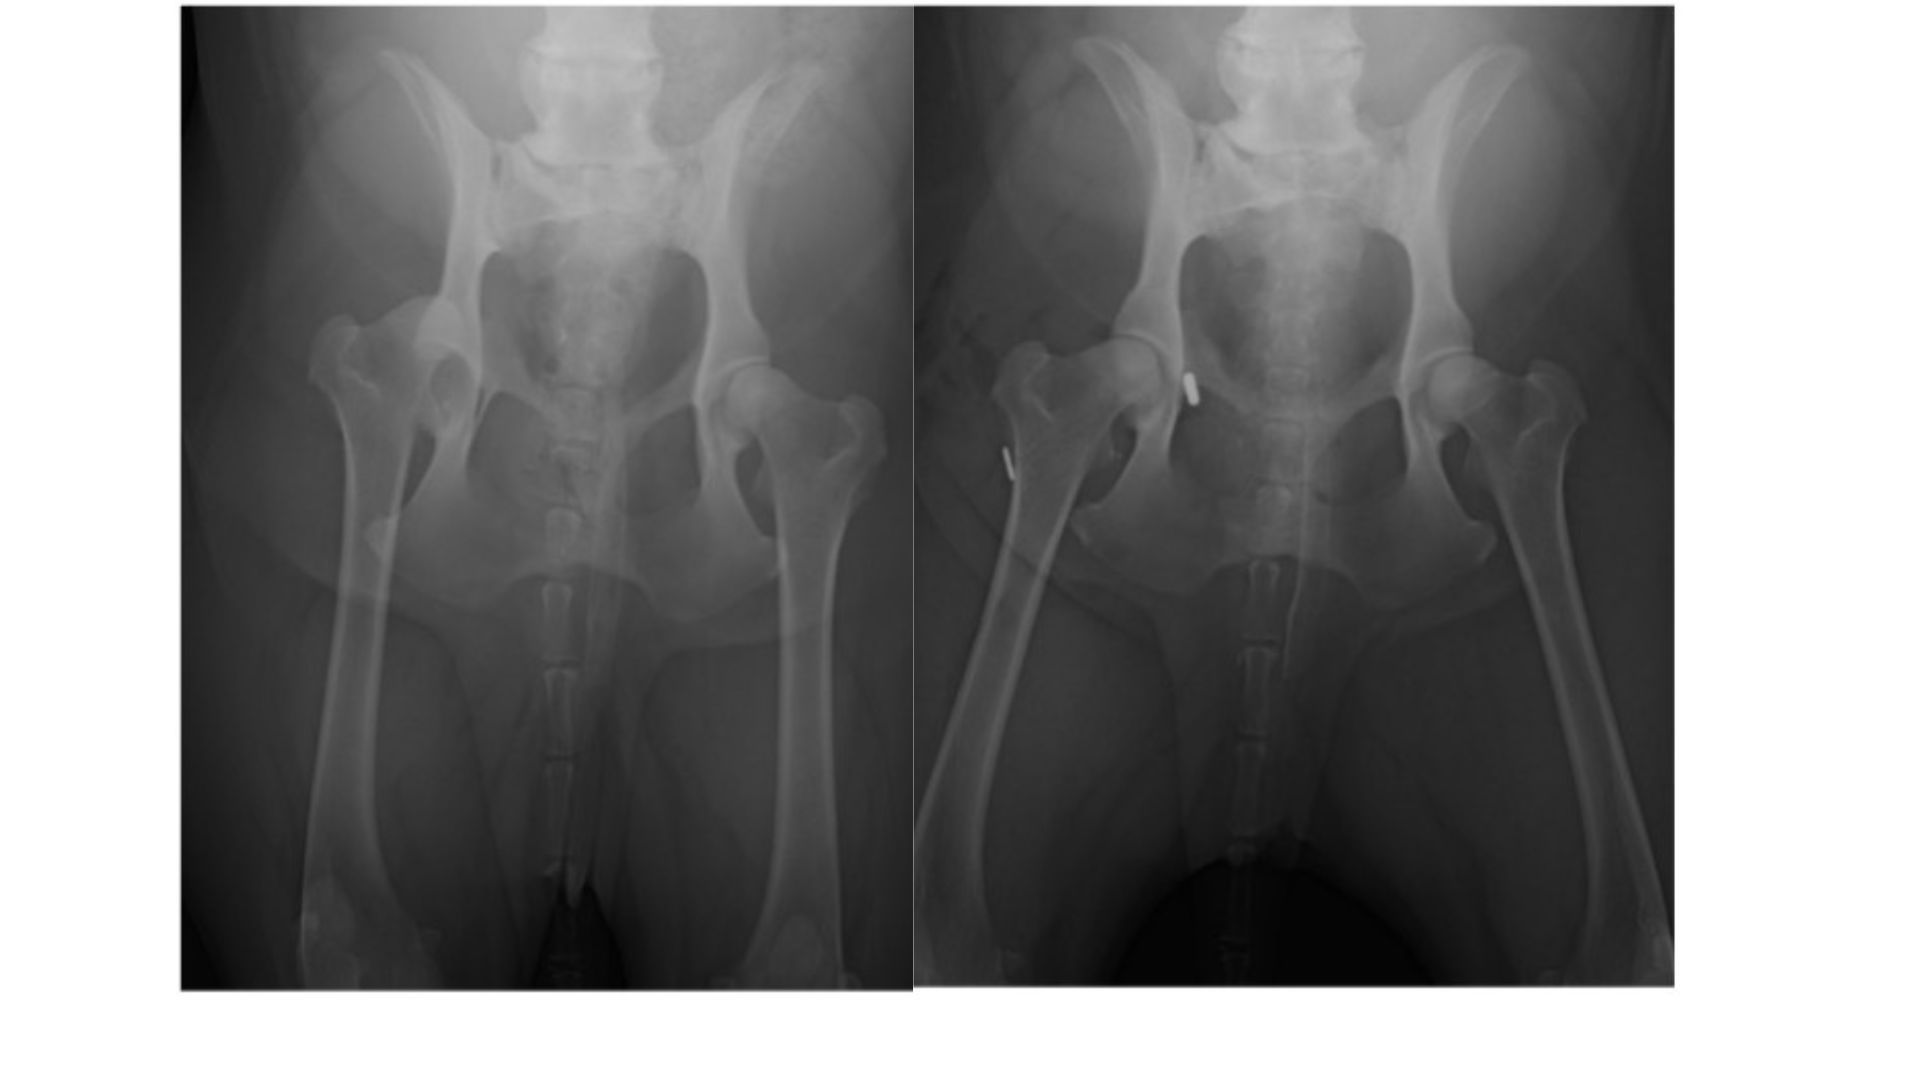

Hip Toggle

When trauma causes hip dislocations, a Hip toggle procedure offers a reliable surgical solution:

- The technique involves drilling tunnels in both the femoral head and hip socket, then passing a synthetic ligament (toggle rod and suture) through them to stabilise the joint

- This mimics the natural ligament’s function and secures the femur in place, often allowing immediate post surgery weight bearing and restoring normal movement

Our veterinarians are always happy to receive referral from other locations for these procedures. In most cases, our veterinarians would perform new radiographs to assist with diagnosis and allow the best possible planning for the procedure that is required.